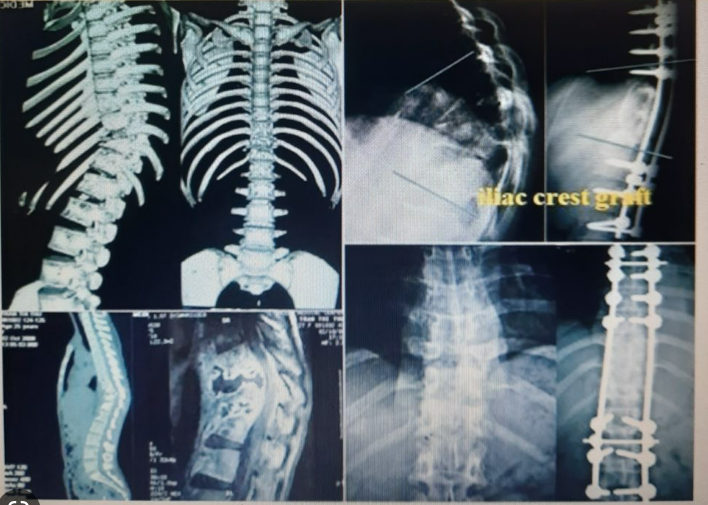

Lao cột sống chiếm khoảng ½ tổng số lao xương khớp. Đối với lao cột sống tổn thương vùng lưng và thắt lưng chiếm 90% các trường hợp. Vi khuẩn lao thường gây tổn thương hai đốt sống trên dưới và đĩa đệm ở giữa. Đây là nguyên nhân gây liệt hai chi dưới do chèn ép tủy và rễ thần kinh.

- Biến dạng xương: gù nhọn, xẹp đốt sống, chèn ép tủy sống, rễ thần kinh.

- CT Scan, MRI: Các phương tiện chẩn đoán hình ảnh này có thể giúp đánh giá tổn thương lao xương trên bệnh nhân cũng như giúp phát hiện các biến chứng của bệnh.